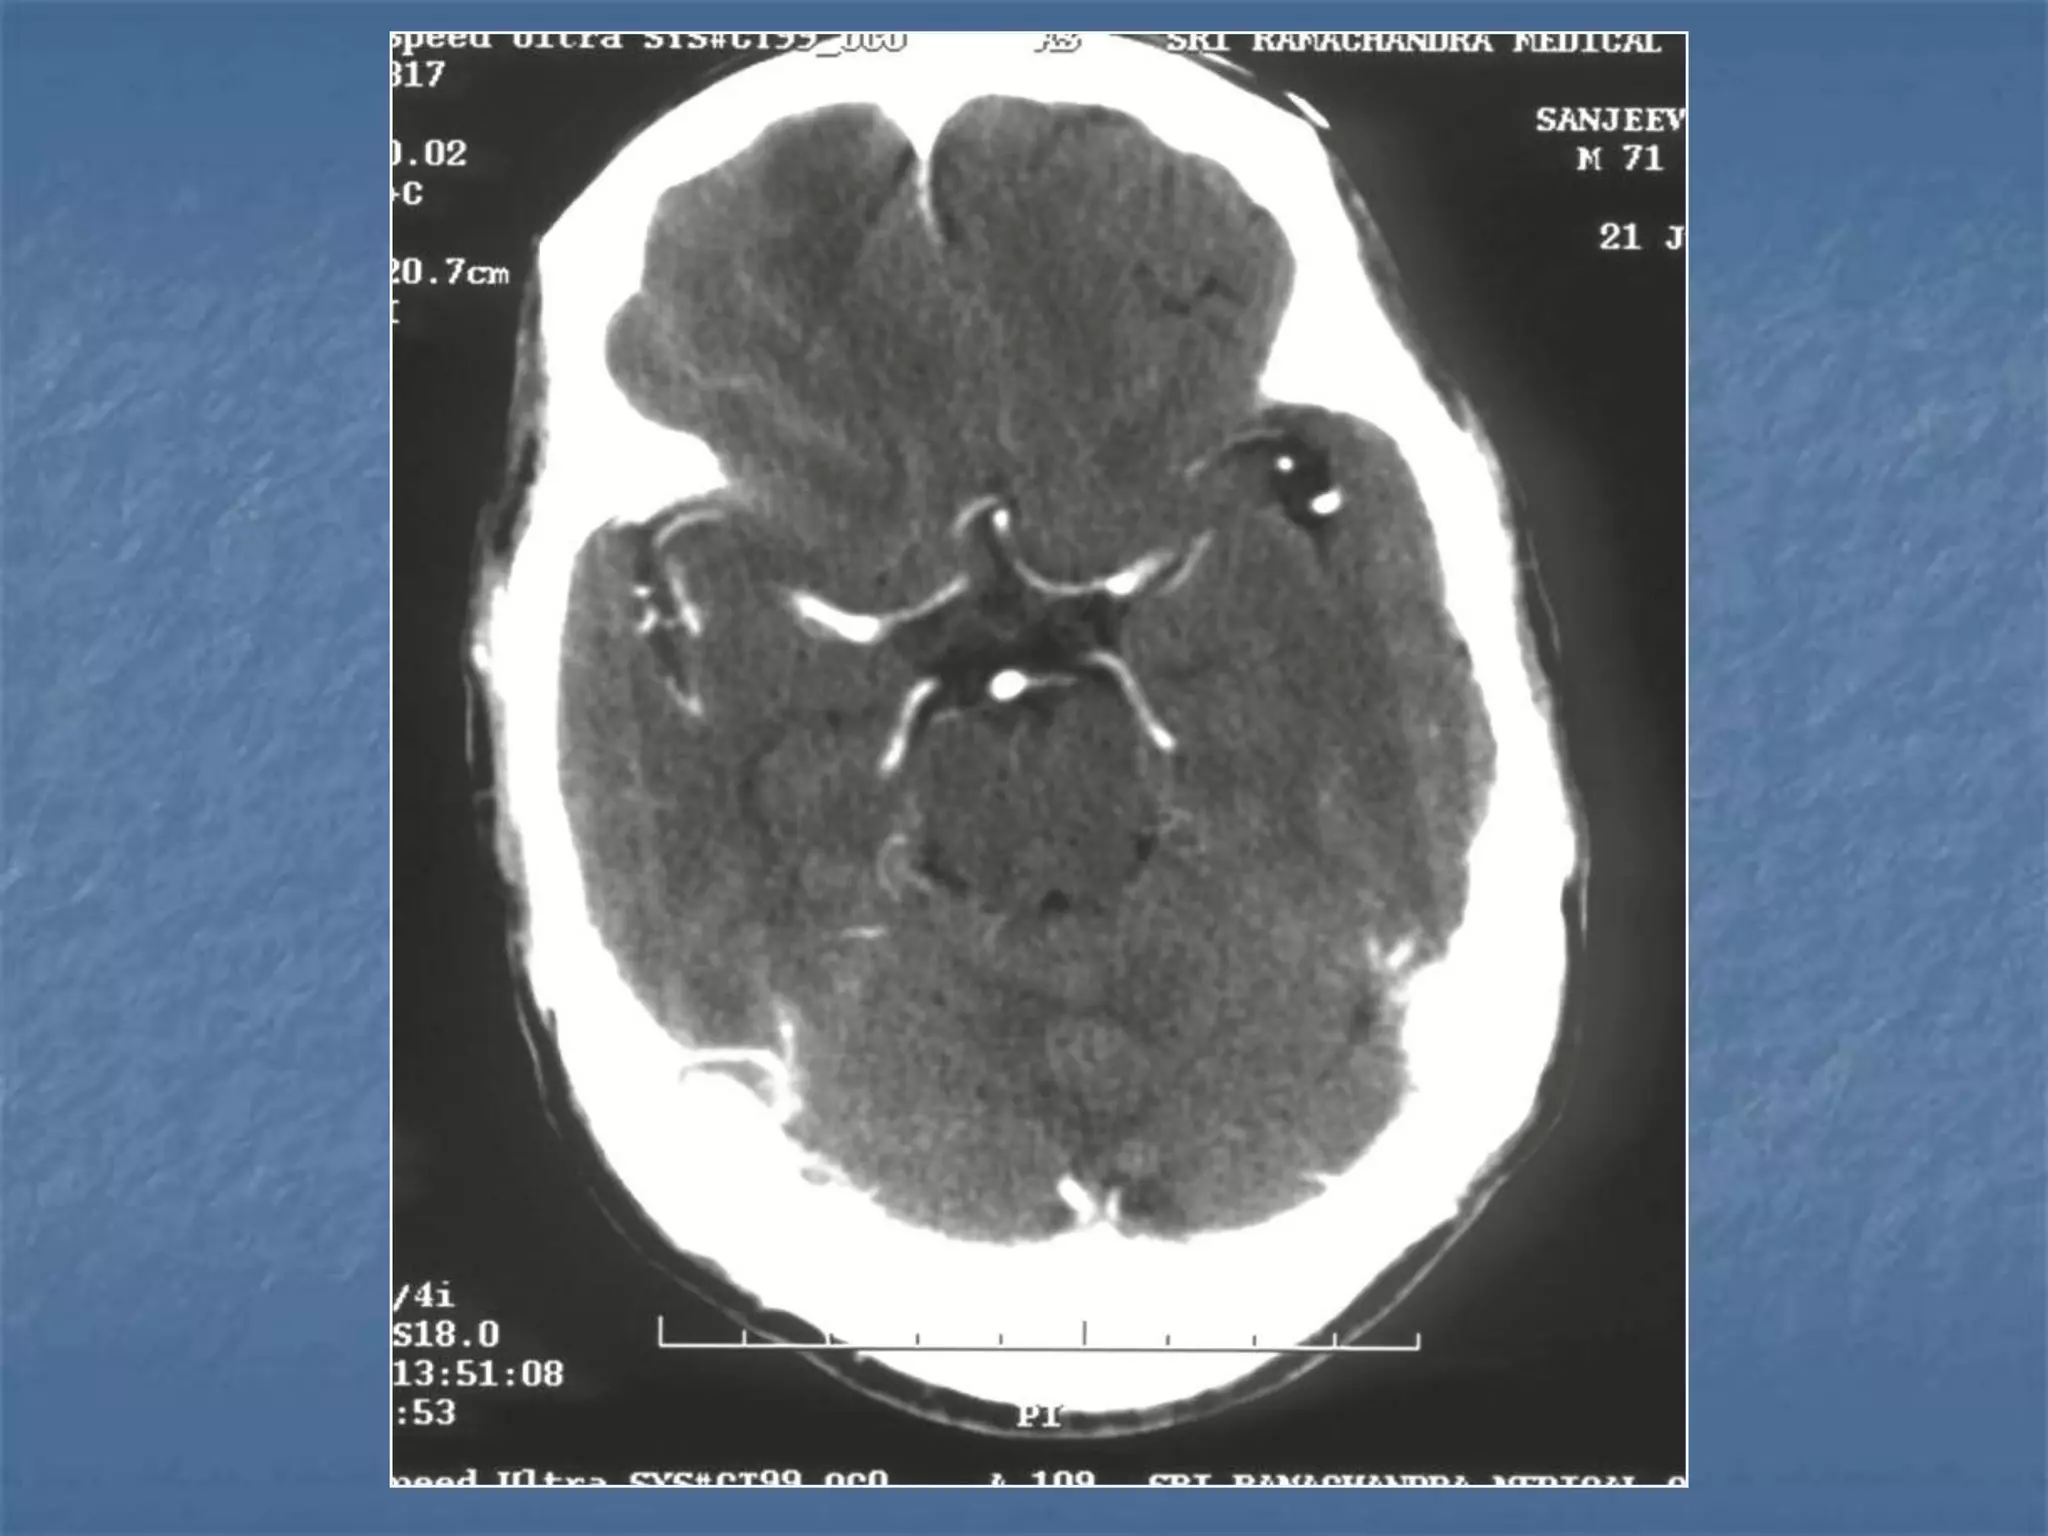

Subarachnoid hemorrhage

 In the absence of trauma, the most common cause

of subarachnoid hemorrhage is a ruptured cerebral

aneurysm. Cerebral aneurysms tend to occur at

branch points of intracranial vessels and thus are

frequently located around the Circle of Willis.

Common aneurysm locations include the anterior

and posterior communicating arteries, the middle

cerebral artery bifurcation and the tip of the basilar

artery. Subarachnoid hemorrhage typically presents

as the "worst headache of life" for the patient.

Detection of a subarachnoid hemorrhage is crucial

because the rehemorrhage rate of ruptured

aneurysms is high and rehemorrhage is often fatal.

 CT is currently the imaging modality of choice because

of its high sensitivity for the detection of subarachnoid

hemorrhage. CT is most sensitive for acute

subarachnoid hemorrhage. After a period of days to

weeks CT becomes much less sensitive as blood is

resorbed from the CSF. If there is a strong clinical

indication, LP may be warranted despite a negative CT

since small bleeds can be unapparent on imaging.

On CT, a subarachnoid hemorrhage appears as high

density within sulci and cisterns. The insular regions

and basilar cisterns should be carefully scrutinized for

subtle signs of subarachnoid hemorrhage.

Subarachnoid hemorrhage may have associated

intraventricular hemorrhage and hydrocephalus.